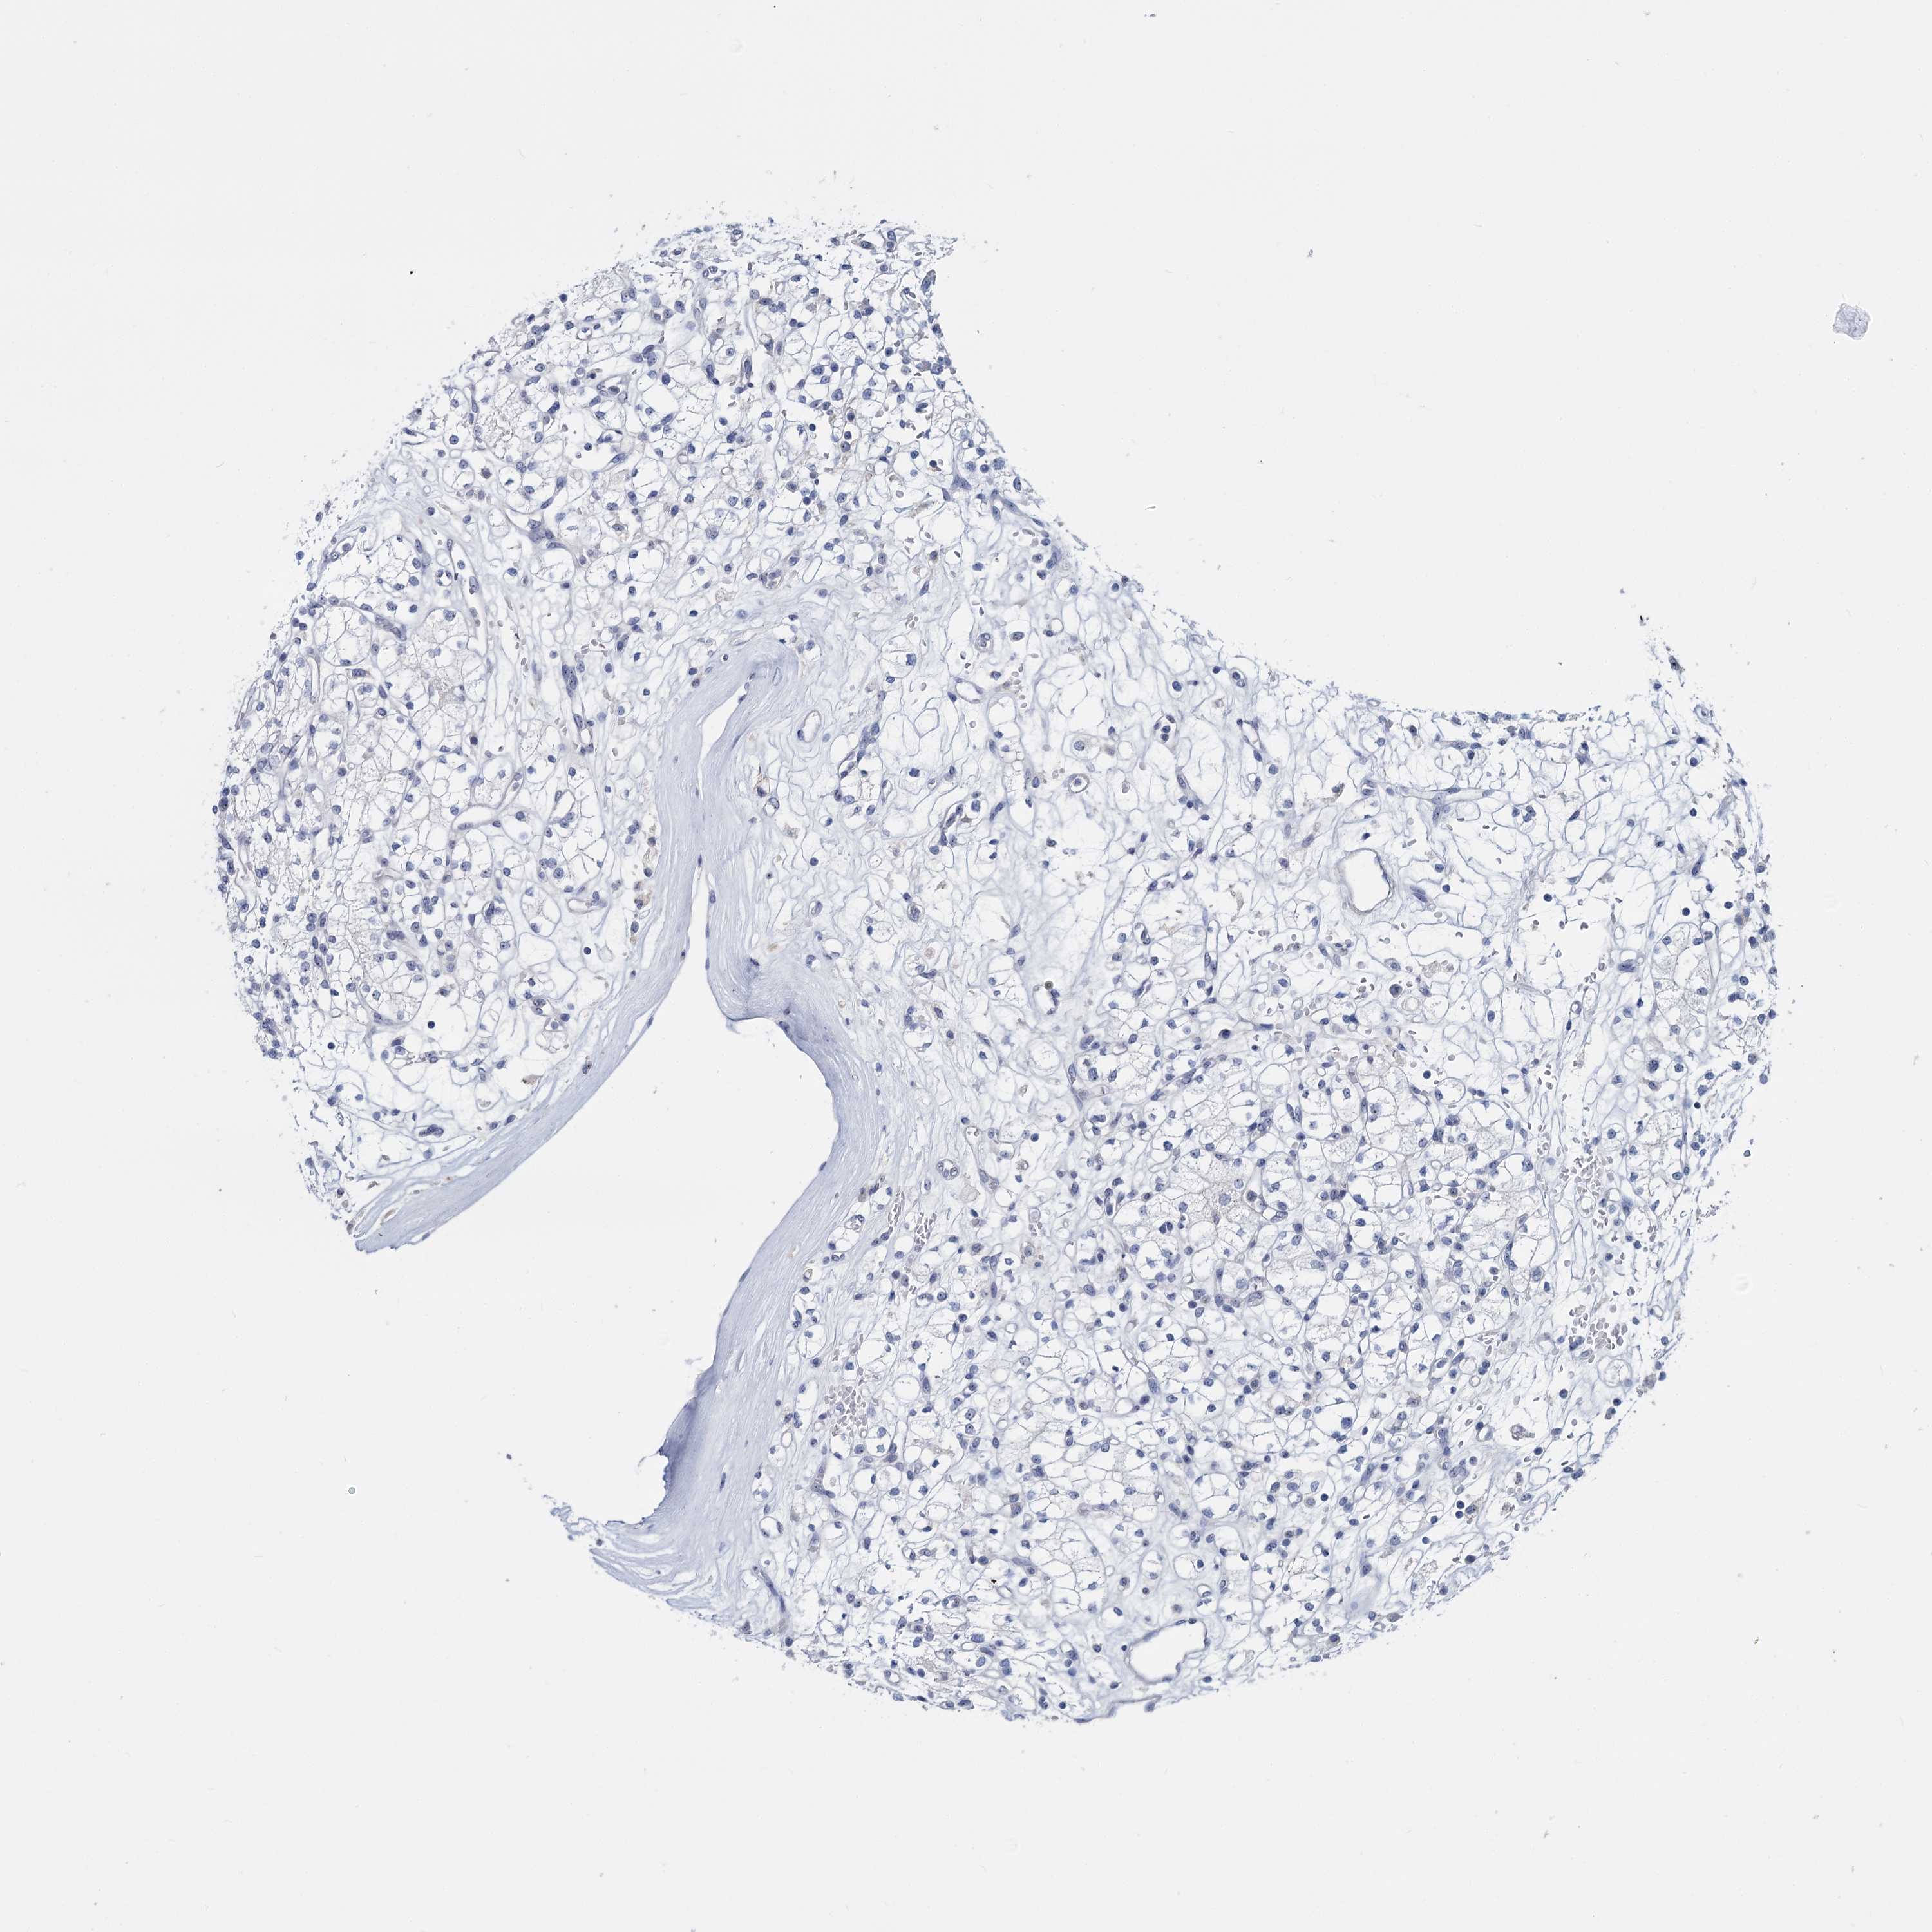

KIDNEY CHROMOPHOBE (TCGA) - Interactive survival scatter ploti

The Survival Scatter plot shows the clinical status (i.e. dead or alive) for all individuals in the patient cohort, based on the same data that underlies the corresponding Kaplan-Meier plots. Patients that are alive at last time for follow-up are shown in blue and patients who have died during the study are shown in red.

The x-axis shows the expression levels (FPKM) of the investigated gene in the tumor tissue at the time of diagnosis. The y-axis shows the follow-up time after diagnosis (years). Both axes are complimented with kernel density curves demonstrating the data density over the axes. The top density plot shows the expression levels (FPKM) distribution among dead (red) and alive patients (blue). The right density plot shows the data density of the survived years of dead patients with high and low expression levels respectively, stratified using the cutoff indicated by the vertical dashed line through the Survival Scatter plot. This cutoff is automatically defined based on the FPKM cutoff that minimizes the p-score. The cutoff can be changed by dragging the vertical line or by entering a cutoff value in the square labeled "Current cut-off".

Under the Survival Scatter plot the p-score landscape (black curve; left axis) is shown together with dead median separation (red curve; right axis). Dead median separation is the difference in median mRNA expression between patients who have died with high and low expression, respectively. It is calculated as follows: median FPKM expression of dead patients with high expression - median FPKM expression of dead patients with low expression. This is intended to aid the user in visually exploring custom cutoffs and the associated p-scores and dead median separation.

Individual patient data is displayed and can be filtered by clicking on one or more of the category buttons on the top of the page. Categories describing expression level and patient information include: high, low, alive, dead, female, male and tumor stages. The scale of the x-axis can be toggled between linear and log-scale by clicking on the "x log" button. Mouse-over function shows TCGA ID, patient information and mRNA expression (FPKM) for each patient.

& Survival analysisi

Kaplan-Meier plots summarize results from analysis of correlation between mRNA expression level and patient survival. Patients were divided based on level of expression into one of the two groups "low" (under cut off) or "high" (over cut off). X-axis shows time for survival (years) and y-axis shows the probability of survival, where 1.0 corresponds to 100 percent.

SFN is not prognostic in Kidney Chromophobe (TCGA)